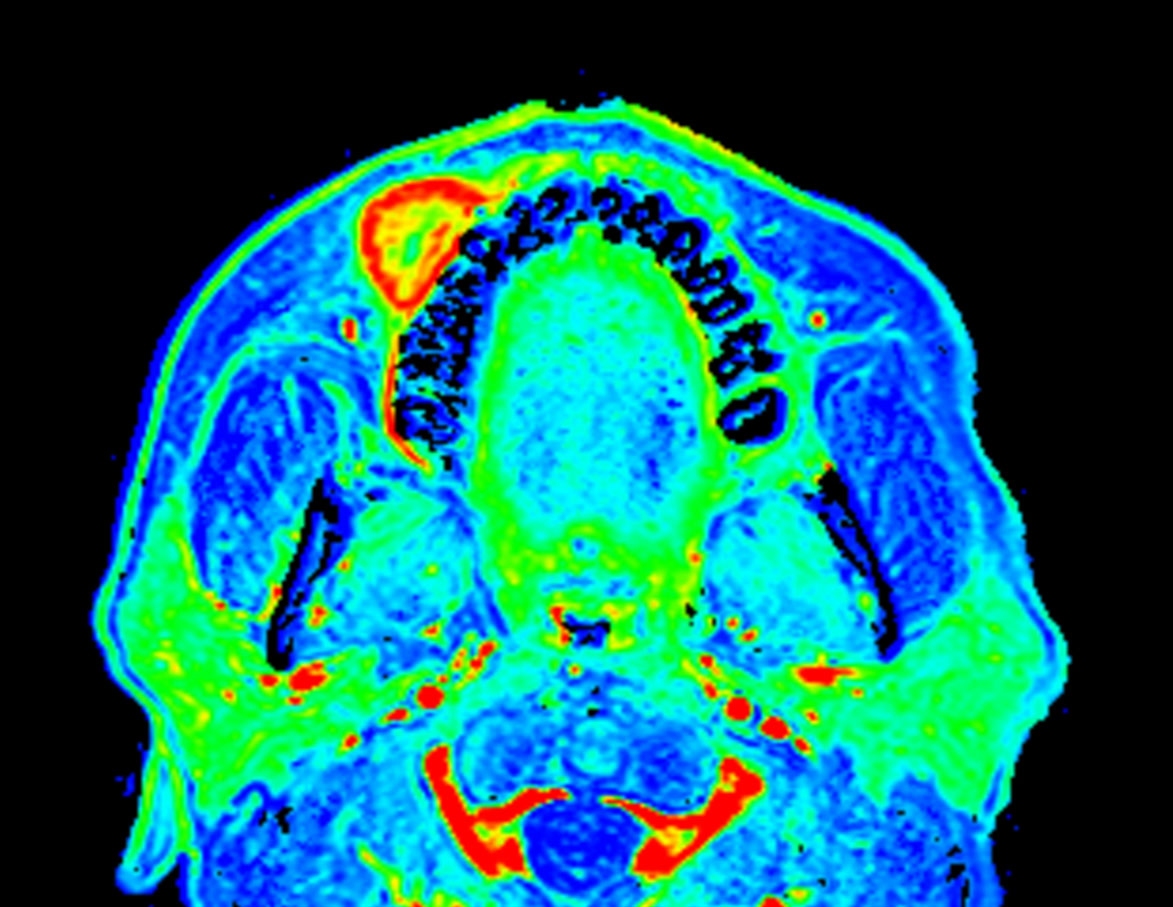

Axial eTHRIVE (area under the curve)

Axial eTHRIVE (max enhancement)

Axial eTHRIVE (wash-in)